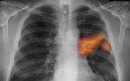

تحقیقات جدید محققان فنلاندی نشان داد: برخی ترکیبات فرار ارگانیک که در گازهای حاصل از برخی مواد جامد و مایع مانند رنگها یافت میشوند در تنفس بیماران مبتلا به سرطان ریه وجود دارند و تجزیه و تحلیل این ترکیبات میتواند به دستیابی به یک ابراز تشخیصی برای این بیماری منجر شود.

بین 350 تا 400 نوع مواد تولید شده مرتبط با شغل، در سلولهای تومورها و سلولهای گروه کنترل کشف شد. مشخص شد که 120 نوع از این ترکیبات در اکثر سلولهای سرطانی و گروه کنترل یافت میشود. از بین این 120 نوع، پنج نوع در تمام سلولهای سرطانی وجود داشتند که در سلولهای گروه کنترل نبودند و سه نوع از آنها در تنفس بیش از 90 درصد بیماران سرطان ریه سلولهای غیر کوچک (NSCLC) یافت شد.

دانشمندان با این یافته میتوانند تستی ابداع کنند که با بررسی تنفس بیماران زمینههای تشخیص زودهنگام سرطان ریه را فراهم آورند.